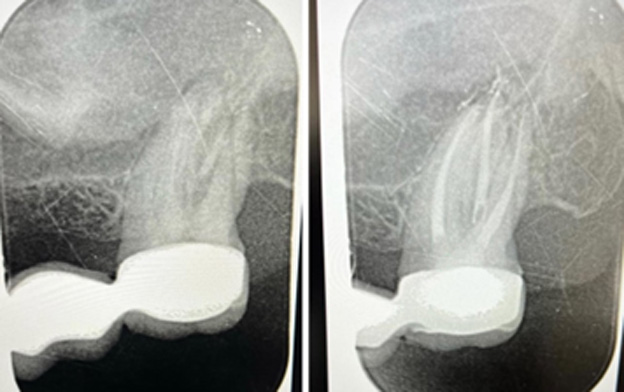

1. Diagnostika a príprava – Lekár urobí röntgenový snímok, aby zistil rozsah poškodenia. Následne podá lokálnu anestéziu, aby bol zákrok bezbolestný. 2. Odstránenie infekcie – Lekár otvorí zub a vyčistí koreňové kanáliky od infikovanej drene. 3. Dezinfekcia a vyplnenie – Priestor vo vnútri zubu sa dôkladne dezinfikuje a vyplní špeciálnym materiálom, ktorý zabraňuje ďalšej infekcii. 4. Obnova zubu – Po endodontickom ošetrení môže zub potrebovať výplň alebo korunku, aby získal späť svoju pevnosť a funkčnosť.